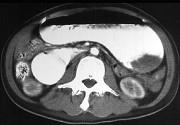

问题 女,14岁,腹胀疼痛,上腹部见胃形,呕吐(胆汁样),影像检查如图,最可能的诊断是 ( )

选项 A.十二指肠综合征 B.机械性小肠梗阻 C.十二指肠憩室 D.十二指肠重复畸形 E.麻痹性肠梗阻

答案 A